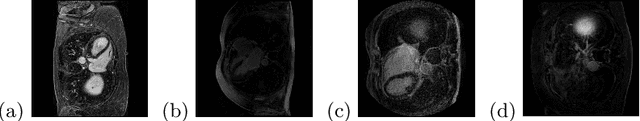

Abstract:Assessment of myocardial viability is essential in diagnosis and treatment management of patients suffering from myocardial infarction, and classification of pathology on myocardium is the key to this assessment. This work defines a new task of medical image analysis, i.e., to perform myocardial pathology segmentation (MyoPS) combining three-sequence cardiac magnetic resonance (CMR) images, which was first proposed in the MyoPS challenge, in conjunction with MICCAI 2020. The challenge provided 45 paired and pre-aligned CMR images, allowing algorithms to combine the complementary information from the three CMR sequences for pathology segmentation. In this article, we provide details of the challenge, survey the works from fifteen participants and interpret their methods according to five aspects, i.e., preprocessing, data augmentation, learning strategy, model architecture and post-processing. In addition, we analyze the results with respect to different factors, in order to examine the key obstacles and explore potential of solutions, as well as to provide a benchmark for future research. We conclude that while promising results have been reported, the research is still in the early stage, and more in-depth exploration is needed before a successful application to the clinics. Note that MyoPS data and evaluation tool continue to be publicly available upon registration via its homepage (www.sdspeople.fudan.edu.cn/zhuangxiahai/0/myops20/).

Abstract:Automatic segmentation of multi-sequence (multi-modal) cardiac MR (CMR) images plays a significant role in diagnosis and management for a variety of cardiac diseases. However, the performance of relevant algorithms is significantly affected by the proper fusion of the multi-modal information. Furthermore, particular diseases, such as myocardial infarction, display irregular shapes on images and occupy small regions at random locations. These facts make pathology segmentation of multi-modal CMR images a challenging task. In this paper, we present the Max-Fusion U-Net that achieves improved pathology segmentation performance given aligned multi-modal images of LGE, T2-weighted, and bSSFP modalities. Specifically, modality-specific features are extracted by dedicated encoders. Then they are fused with the pixel-wise maximum operator. Together with the corresponding encoding features, these representations are propagated to decoding layers with U-Net skip-connections. Furthermore, a spatial-attention module is applied in the last decoding layer to encourage the network to focus on those small semantically meaningful pathological regions that trigger relatively high responses by the network neurons. We also use a simple image patch extraction strategy to dynamically resample training examples with varying spacial and batch sizes. With limited GPU memory, this strategy reduces the imbalance of classes and forces the model to focus on regions around the interested pathology. It further improves segmentation accuracy and reduces the mis-classification of pathology. We evaluate our methods using the Myocardial pathology segmentation (MyoPS) combining the multi-sequence CMR dataset which involves three modalities. Extensive experiments demonstrate the effectiveness of the proposed model which outperforms the related baselines.